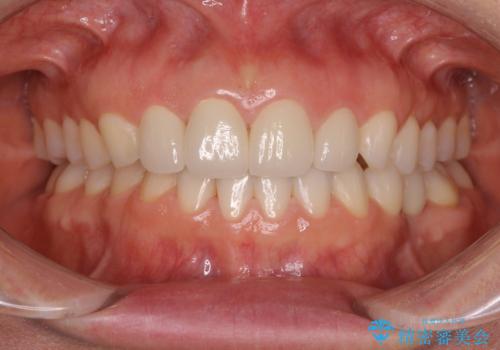

オープンバイトでかみにくい インビザラインによる矯正治療

- 前歯の上下スペースによる食べにくさを気にして来院された患者様です。

インビザラインにより上下の前歯の隙間を閉じていくこととしました。

上下の奥歯を圧下させるようにすることで、前歯を接触させるように計画しました。

上下の隙間に舌が入り込むことがオープンバイトの原因であったため、舌の筋肉のトレーニングも並行して行い、後戻りの抑制を図りました。